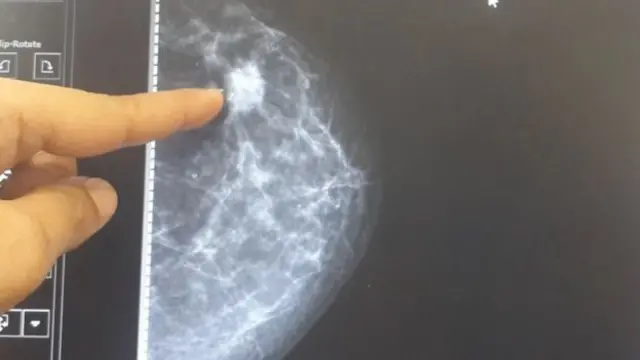

अधिक वज़न वाली महिलाओं में स्तन कैंसर की गांठों का पता वक्त पर नहीं चल पाता. ऐसे मामलों में जब गांठ बहुत बड़ी हो जाती है तब पता चल पाता है. ये बात स्वीडन के शोधकर्ताओं के एक अध्ययन में पता चली है.

शोधकर्ताओं का कहना है कि मोटी महिलाओं के स्तन कैंसर का पता लगाने के लिए कम समय के अंतराल में जांच (मैमोग्राम) कराते रहना चाहिए. ताकि सही समय पर गांठों का पता लगाकर इलाज किया जा सके.

ये महिलाएं हर 18 महीने से दो साल के बीच मैमोग्राम कराती थीं. स्वीडन में इतने अंतराल को मानक माना जाता है.

शोधकर्ताओं ने इलाज के दौरान गांठ का आकार और महिला के बॉडी मास इंडेक्स (मोटापे का पैमाना) का अध्ययन किया.

टीम ने पाया कि ज़्यादा वज़न वाली महिलाओं में मैमोग्राम जांच के समय गांठ का पता चला.

अध्ययन की अगुवाई कर रहे फ़्रेड्रिक स्ट्रैंड ने बीबीसी को बताया कि ऐसा शायद इसलिए हुआ क्योंकि मोटी महिलाओं के स्तन ज्यादा बड़े थे, इसलिए गांठ का पता लगाना मुश्किल था. या फिर उनमें गांठ तेज़ी से विकसित हुई.